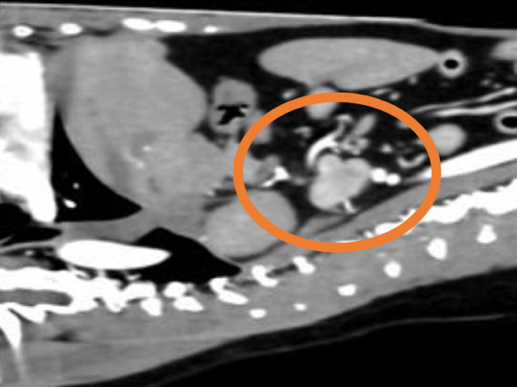

膀胱結石の精査目的で他院にてCT検査を実施したところ、左副腎に腫瘍性病変が認められ、後大静脈への浸潤も確認されました。 これを受けて、手術目的で当院を受診されました。 当院にて褐色細胞腫摘出術を実施し、術後は体調良好であったため、術後4日目に退院されました。

手術前のCT検査にて腫瘍の浸潤・転移チェックを実施